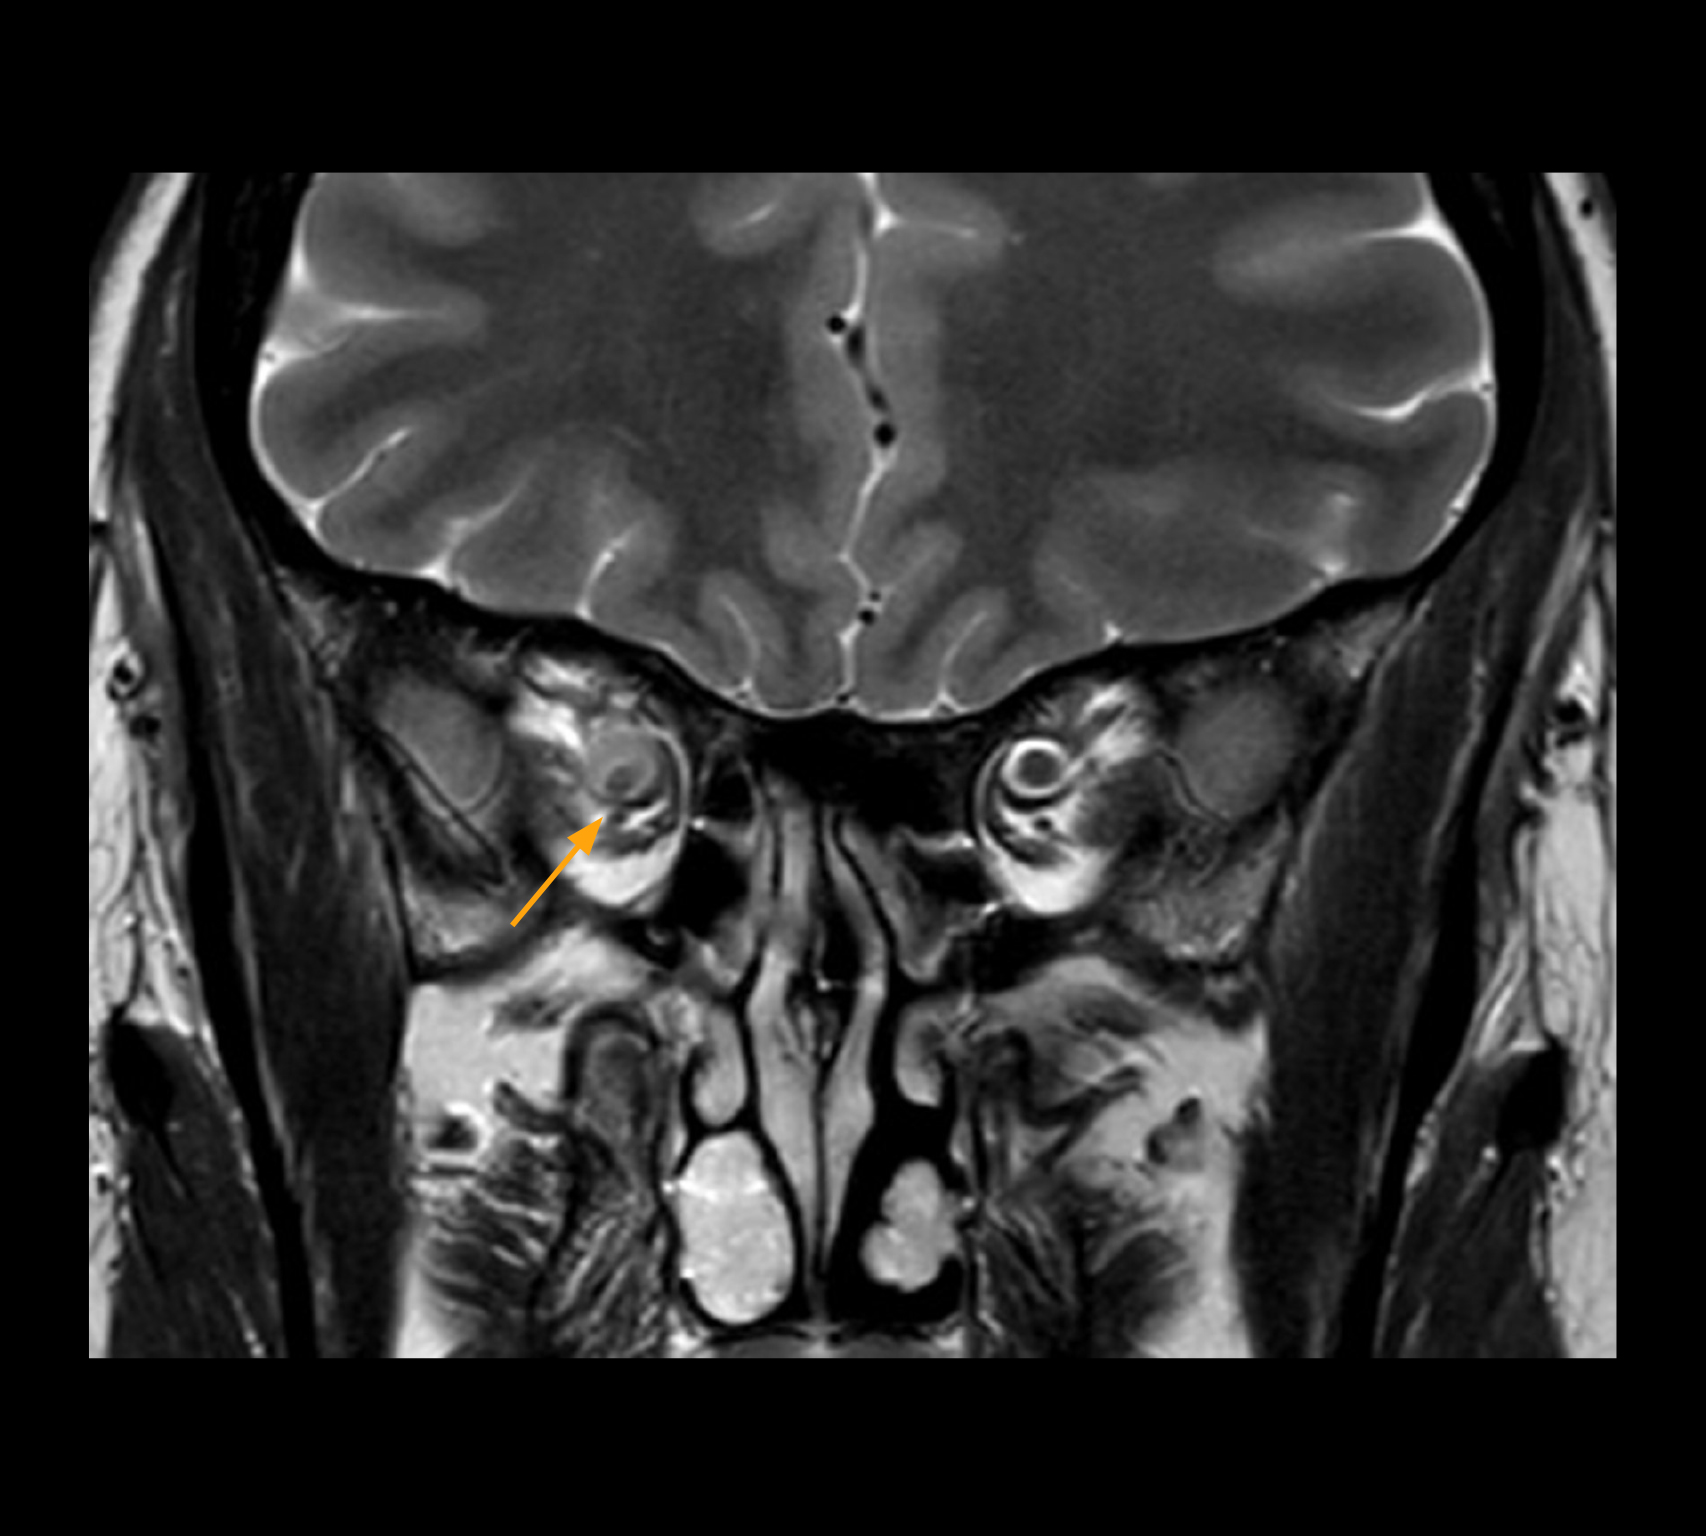

In select cases, the MR 7700 has helped the hospital’s physicians more clearly visualize pathology. “We’re definitely getting the impression that tumors are better delineated with the MR7700,” Dr. Heindel says. “For example, I examined a patient who had been diagnosed in another hospital with possible neuritis of the optic nerve. However, the MR 7700 images allowed me to diagnose it as an optic nerve sheath meningioma, a rare and often misdiagnosed, slowly growing tumor that wascausing the visual disturbances in the patient. The lesion was so well delineated on the high resolution MR 7700 images that our neurosurgeon decided he did not need a biopsy before proceeding directly with decompression of the optic canal and peeling away those tumor cells.”

High-resolution MRI impressively demonstrates the compression and narrowing of the right optic nerve in this case of optic nerve sheath meningioma (ONSM). The coronal T2-weighted images show the hyper-intense, half-moon shaped lesion, that is clearly visible in the axial T1W image after contrast injection (right). These imaging findings were so convincing that there sponsible neurosurgeon did not consider a pretherapeutic histological clarification.